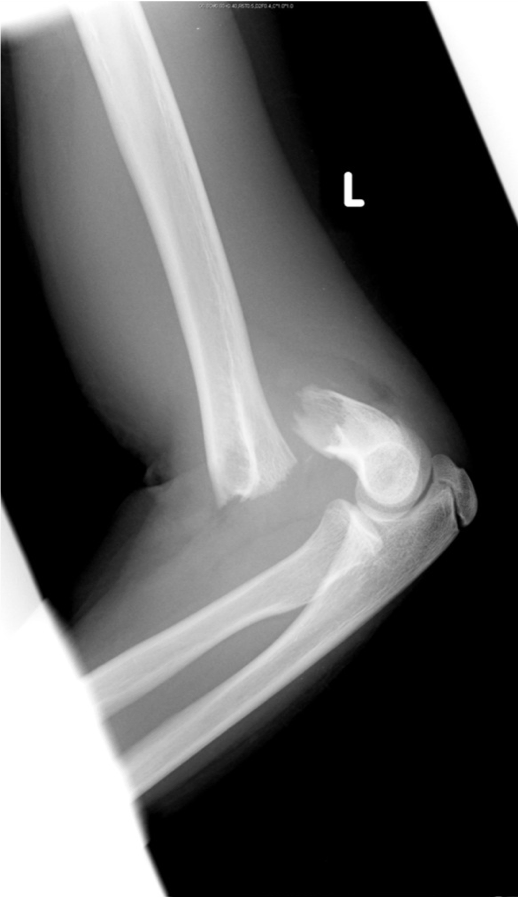

Clinical case: A 13 year old boy fell whilst playing with friends. His left arm was very painful and swollen.

What injury has been sustained?

What structures are vulnerable to injury?

How would you examine this patient?